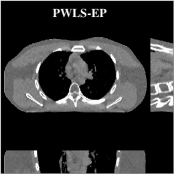

Recent works applied learned unions of transforms to other applications. For example, the union of transforms model was pre-learned (from a dataset) and used in a clustering-based low-dose 3D CT reconstruction scheme [26]. Fig. 4 shows an example of high quality reconstructions obtained with this scheme. While the work used a PWLS-type reconstruction cost, a more recent method [132] replaced the weighted least squares data-fidelity term with the shifted-Poisson likelihood penalty, which further improved image quality and reduced bias in the reconstruction in ultra low-dose settings. Other recent works combined learned union of transforms models with material image models and applied it to image-domain material decomposition in dual-energy CT with high quality results [137, 138].